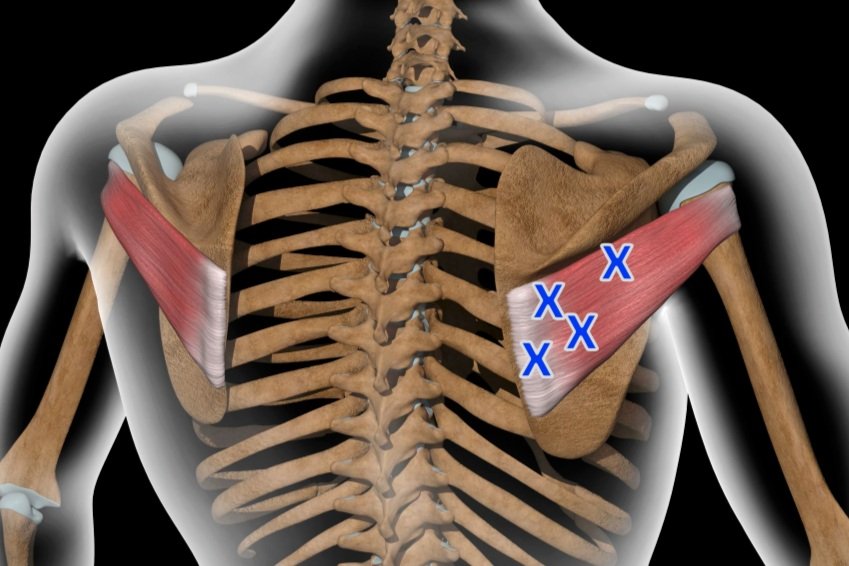

Treating Pectoralis Major Muscle Pain

Explore the causes of pectoralis major muscle pain, learn how pectoralis major trigger points contribute, and discover effective treatments like acupuncture and dry needling.